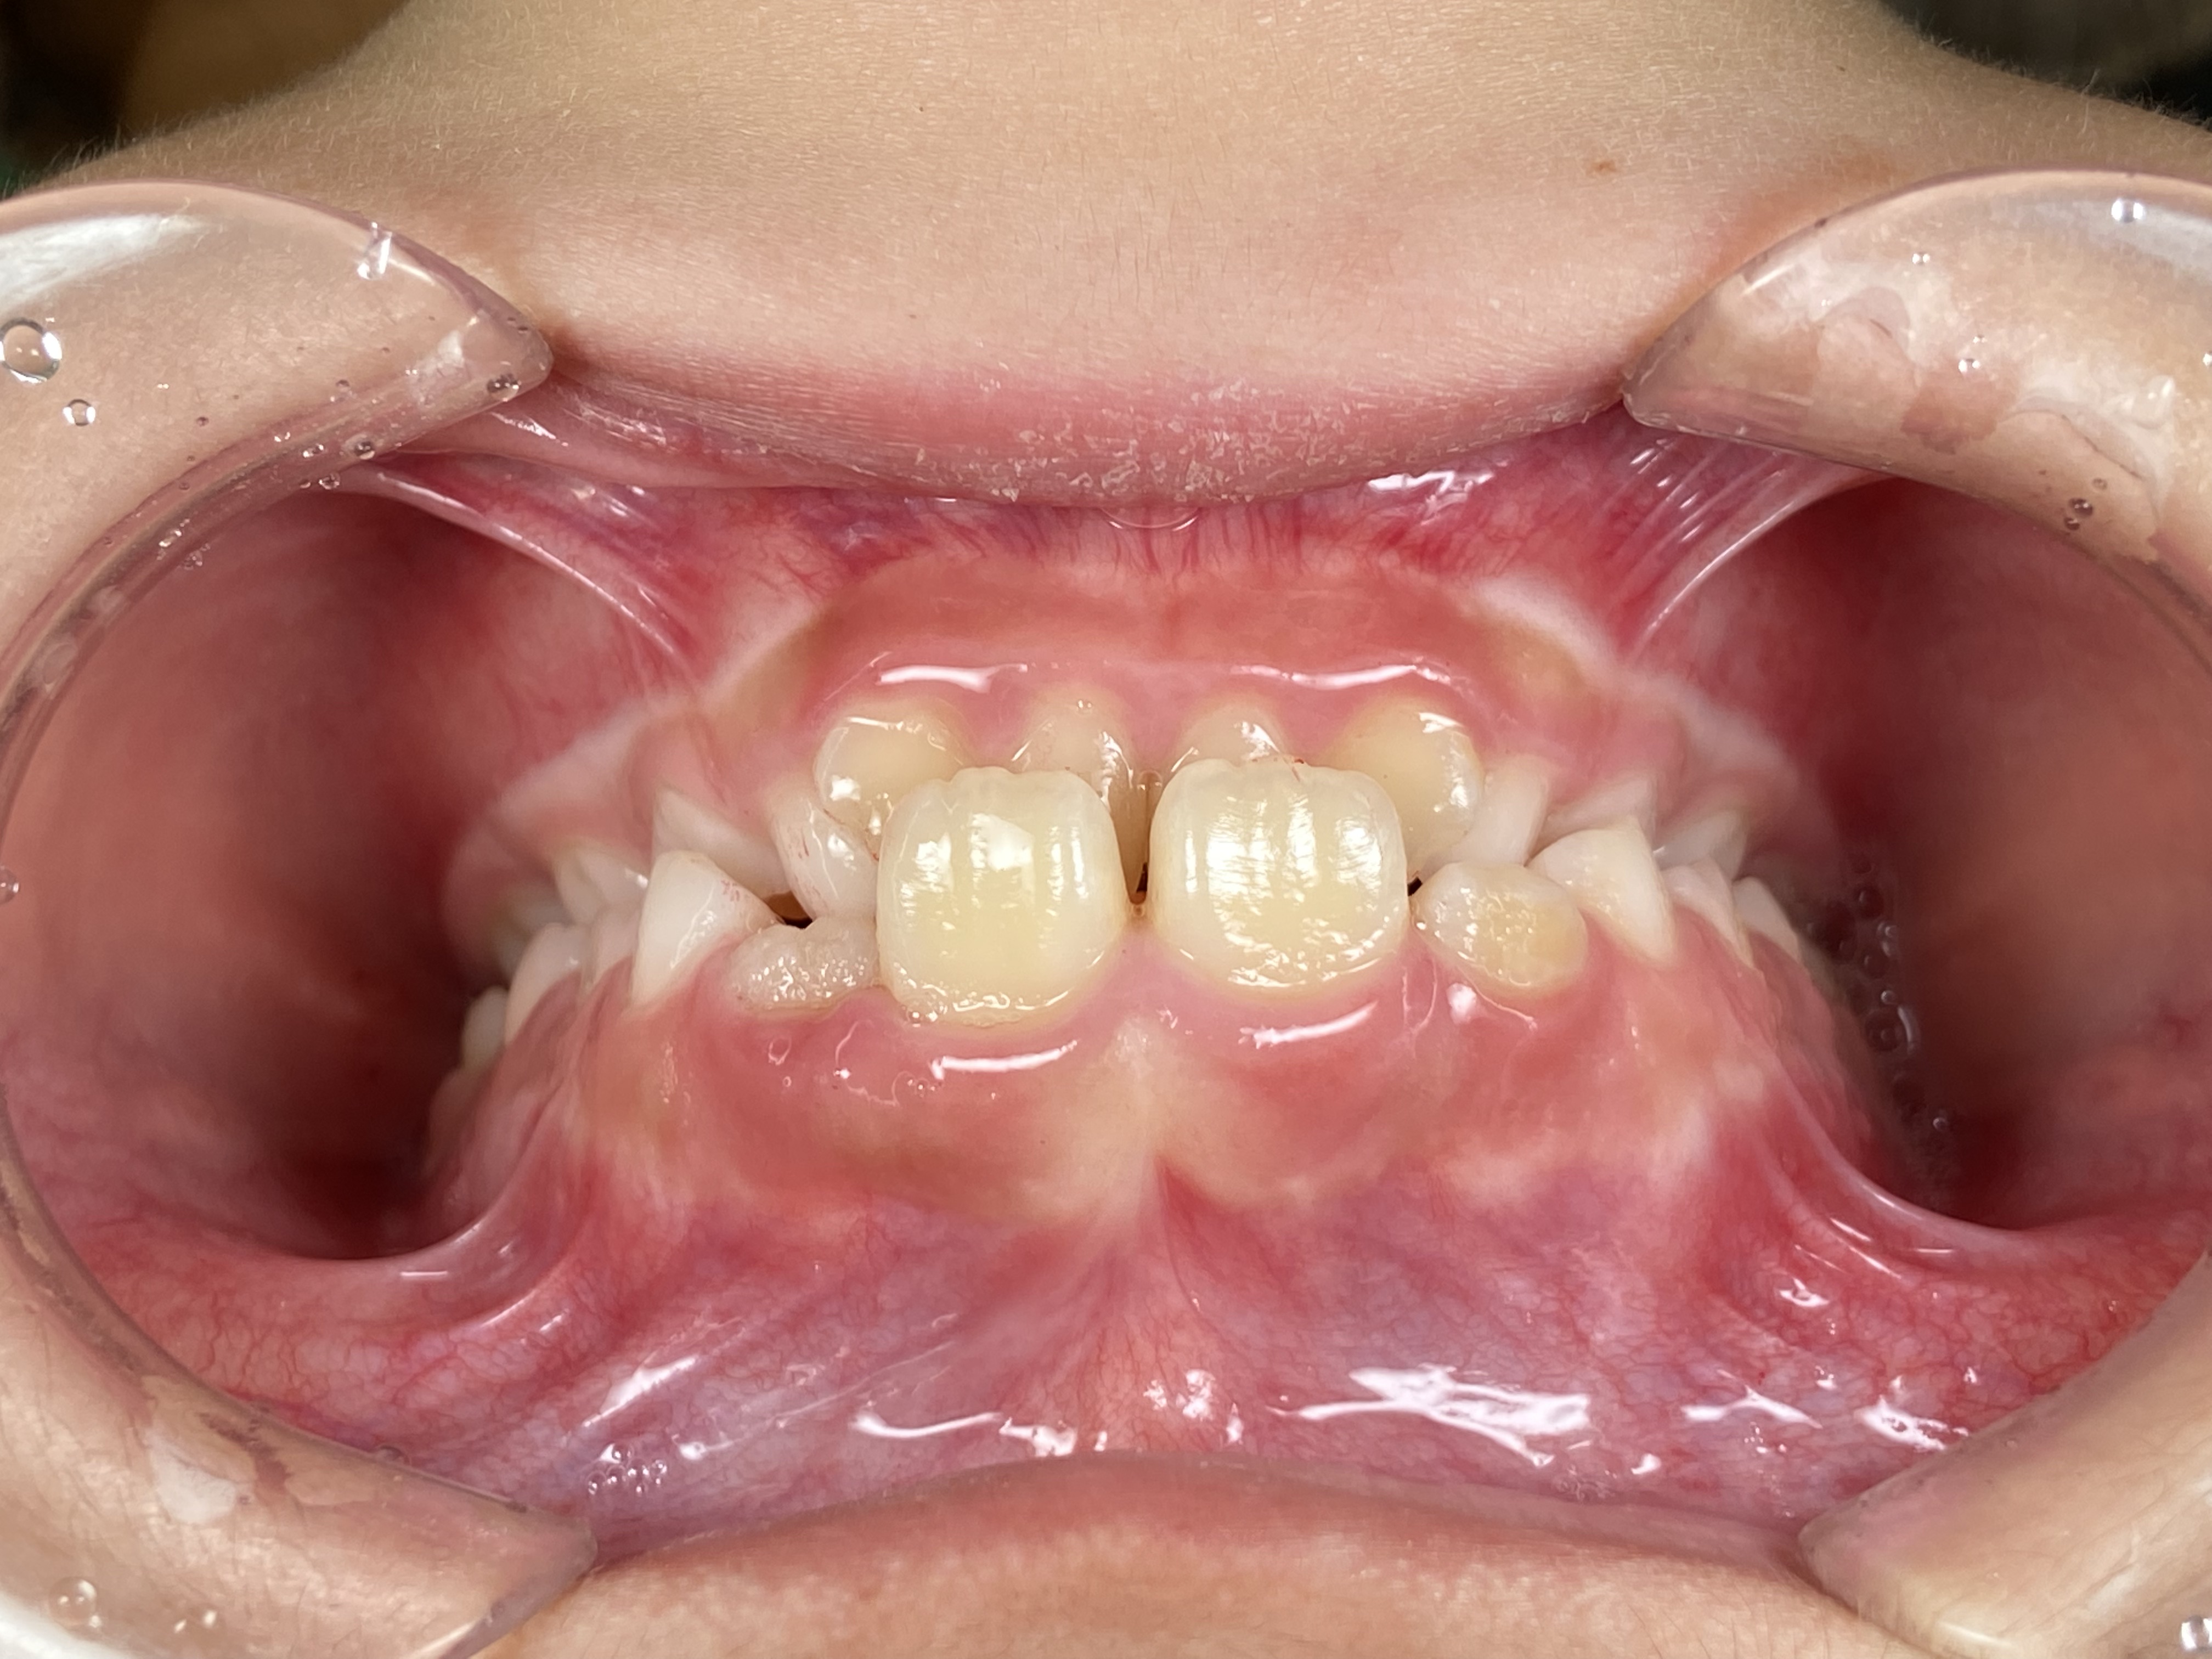

インビザラインファースト症例|上の前歯に隙間があって気になる

2026/02/21 小児矯正